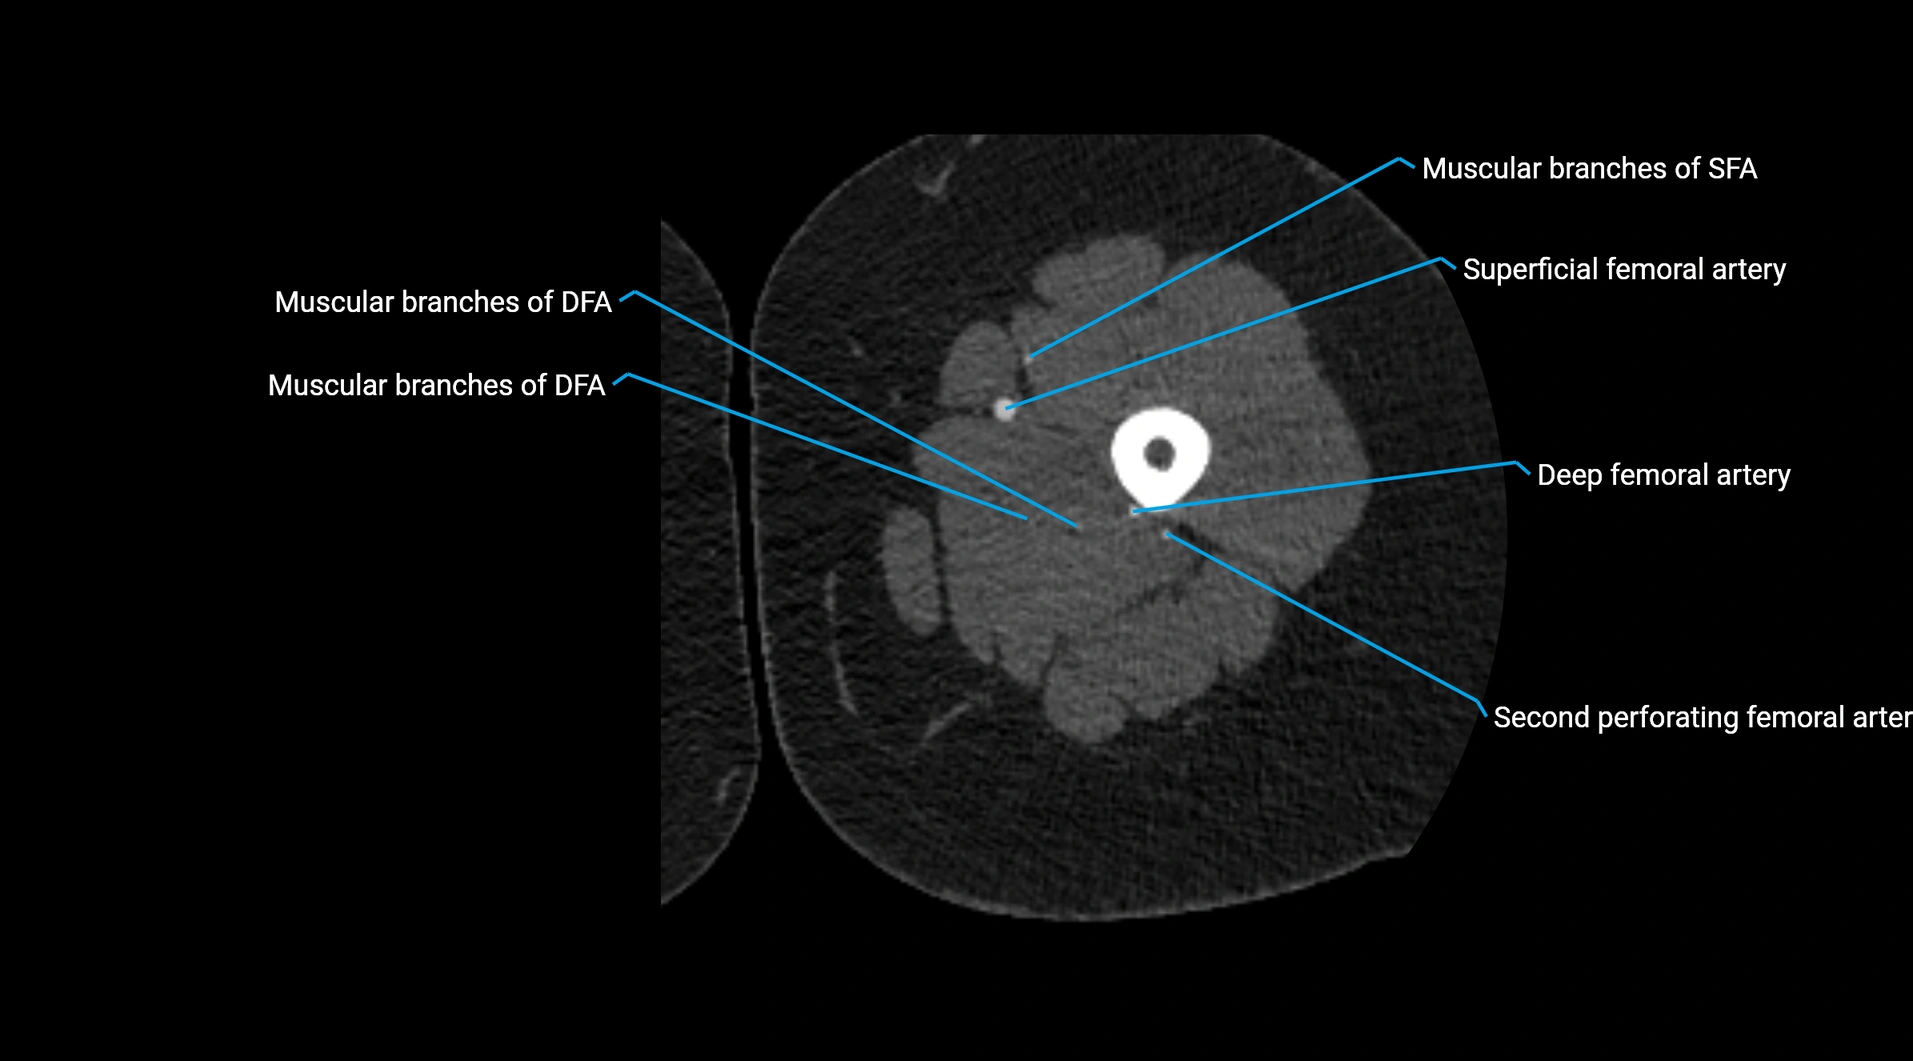

Contrast-enhanced CT (CTA):

• Gold standard for abdominal aortic imaging

• Provides excellent detail of lumen, wall, aneurysm, thrombus, and branch vessels

• Multiplanar and 3D reconstructions help in aneurysm measurement, stent graft planning, and dissection evaluation